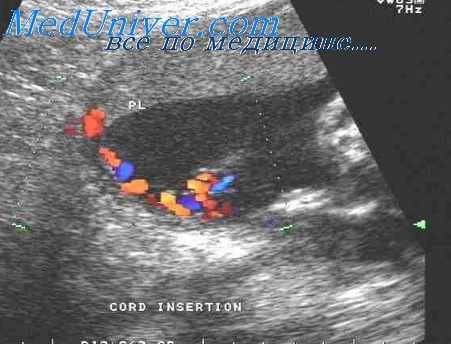

Последние исследования позволили предположить, что плоды с недостаточной спирализацией сосудов пуповины имеют более высокий риск аномалий кариотипа и другой патологии по сравнению с контрольной группой. Для оценки степени спирализации сосудов может использоваться цветовая допплерография, с помощью которой легко определяется количество оборотов артерий вокруг вены пуповины на единицу ее длины.